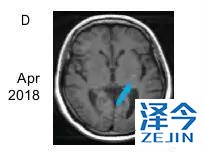

患者再次基因检测发现T790M-C797S顺式突变,因此在2017年7月开始联合使用布加替尼(90mg/日)和西妥昔单抗(600mg/月),治疗一个月时,患者的疲劳和呼吸困难明显改善,CA125水平明显下降,直到2018年4月病情一直稳定(PFS为9个月),除了轻度疲劳外无其他的不良反应。虽然在2018年4月患者出现脑转移灶,但在2018年9月,患者的胸部病灶依旧得到很好的控制。